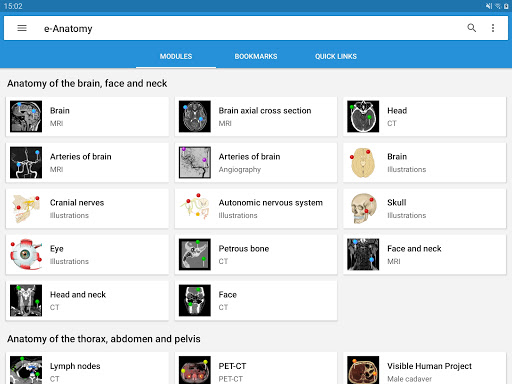

IMAIOS e-Anatomy adalah atlas anatomi manusia untuk dokter, ahli radiologi, mahasiswa kedokteran, dan teknisi radiologi. Dapatkan cuplikan lebih dari 26.000 gambar medis dan anatomi secara gratis sebelum berlangganan atlas anatomi manusia terperinci kami.

e-Anatomy didasarkan pada atlas daring IMAIOS e-Anatomy yang telah memenangkan penghargaan. Bawalah referensi anatomi manusia terlengkap, ke mana pun Anda pergi, di perangkat seluler atau tablet Anda.

e-Anatomy memiliki lebih dari 26.000 gambar yang berisi serangkaian gambar dalam tampilan aksial, koronal, dan sagital serta radiografi, angiografi, gambar diseksi, bagan anatomi, dan ilustrasi. Semua gambar medis diberi label dengan cermat, lebih dari 967.000 label tersedia dalam 12 bahasa termasuk Terminologia Anatomica Latin.

Baru : Sekarang Anda dapat memfilter modul berdasarkan wilayah atau jenis konten sehingga Anda dapat menemukan modul yang Anda cari lebih cepat.